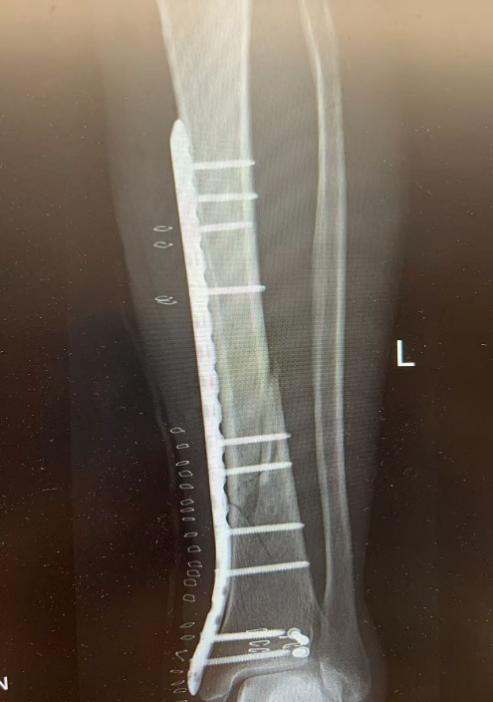

10月4日,59岁张先生不慎被他人电瓶车撞伤致左踝、左小腿疼痛,来院就诊后,王建伟医师团队为患者实行“左胫骨骨折切开复位内固定术”

图片